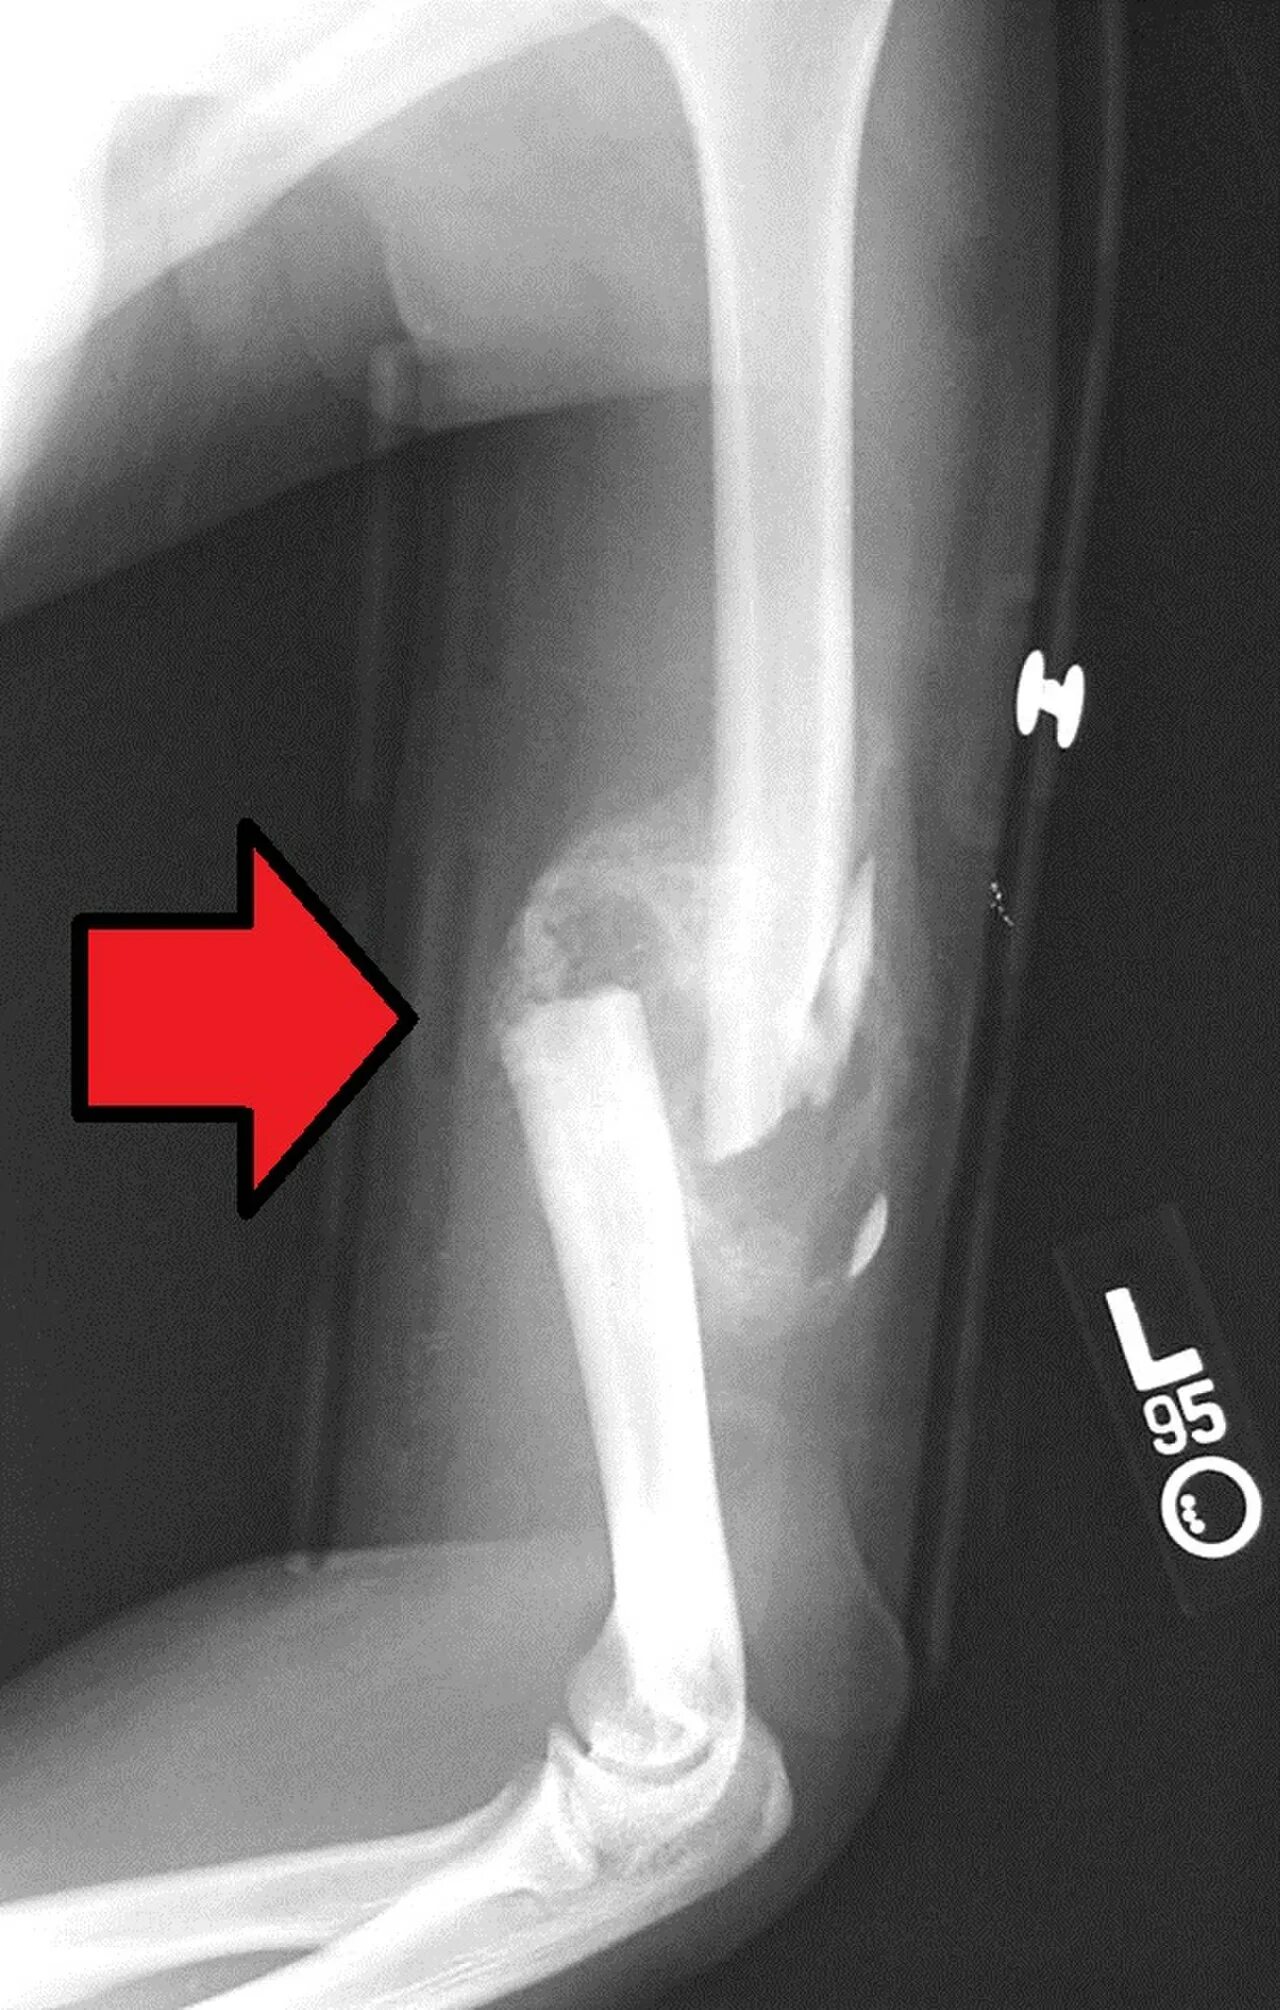

Формирование мозоли при переломе